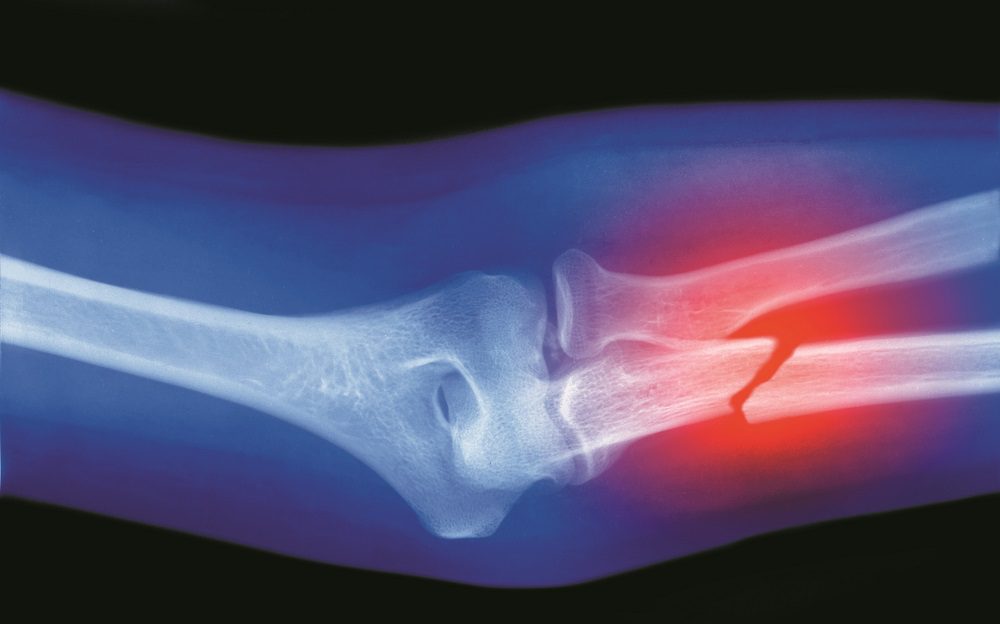

In addition to hips, broken ribs, vertebrae and upper-arm and upper-leg bones are associated with increased mortality rates. Breaks to bones located farther from the torso, including hands, feet, ankles, wrists and forearms, were not associated with increased mortality rates.